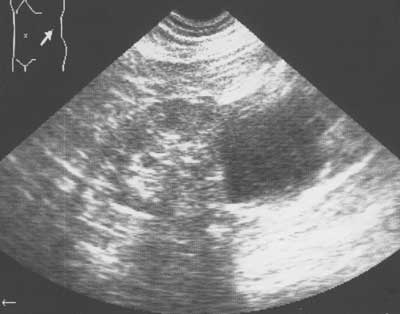

Рис. 5. Эхограмма левой почки. В полость кисты введен этиловый спирт. В полости кисты определяется жидкость.